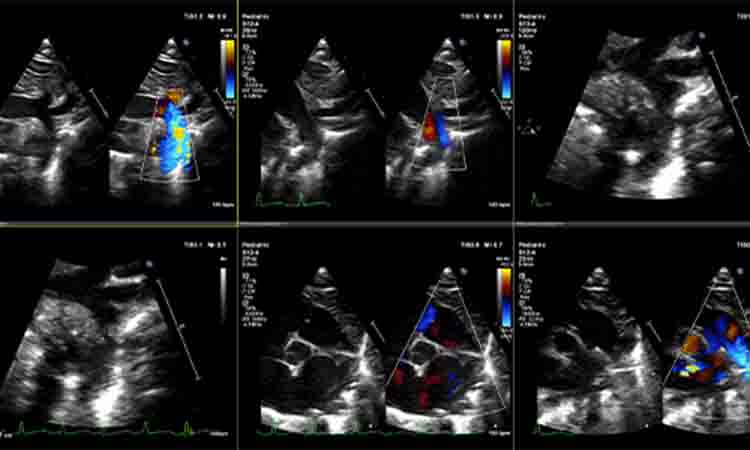

Pediatric/Fetal Echo

Provides all the benefits of our adult echocardiography app, but is refined to meet the needs of pediatric and fetal studies, our Pediatric Echo app is optimized for use with Z scores calculated from many published sources and with a strong emphasis on congenital defects.